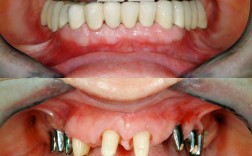

全口/半口种植解决方案:

- 原理: 对于严重骨量不足的全口或半口缺牙,采用特殊的设计和技术,减少对骨量的依赖。

- 类型:

- All-on-4/All-on-6: 在颌骨仅植入4颗或6颗种植体(通常倾斜植入以避开骨量不足区),利用种植体间的角度和力学支撑,安装固定式整排牙桥。这是解决严重骨量不足(尤其是上颌)非常有效且常用的方法。